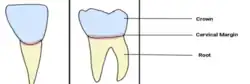

Cervical margins

The cervical margins of teeth are the surfaces where the crown and root meet, and is also referred to as the tooth's neck or cervical line.[1]

The cervical margin, also known as the cervical line or neck of the tooth, represents the boundary between the enamel covering the crown and the cementum covering the root. The cementum typically overlaps the enamel, although in some cases, it may meet edge-to-edge.[2]